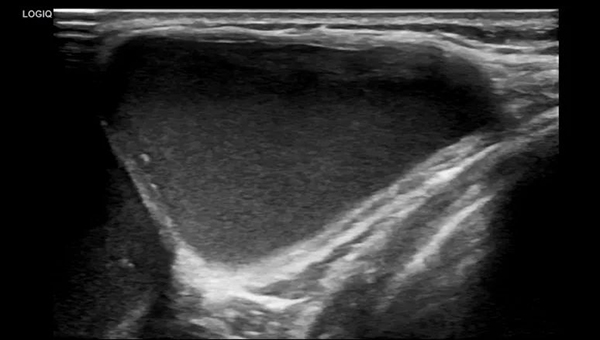

由于淋巴管畸形可发生在身体的任何部位,大多数发生在头颈部,其次为腋窝、纵膈及四肢。通常进行超声、磁共振、CT、诊断性抽液等检查,必要时依据情况进行穿刺活检,基本可以确诊。当怀疑患有淋巴管畸形时,应首先做超声检查,查清楚病变的部位、性质、大小及与周围组织的关系,评估是否需要治疗以及如何治疗。

淋巴管畸形超声:精准定位病灶部位范围以及与周边脏器的关系